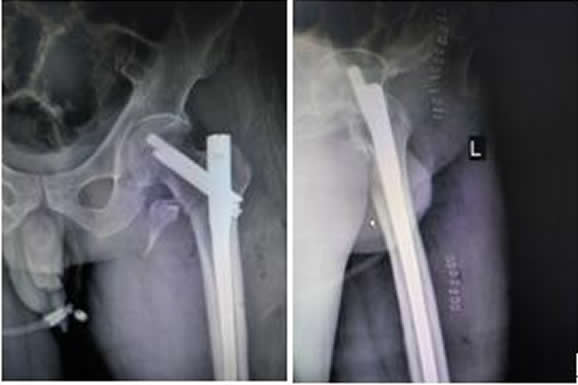

患者稅某某,男,26歲,以“外傷致左髖疼痛、活動受限2小時余”之主訴入院,入院診斷:左股骨近端骨折(A1)。患者于2016.9.19在硬腰聯(lián)合麻醉下行骨折閉合復位InterTan內固定術。手術順利,術后患者恢復良好,現(xiàn)已出院。術后復查拍片如下:

左髖關節(jié)正側位X線片